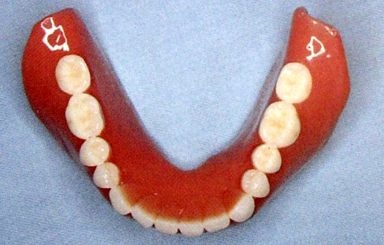

6.磨牙后垫(retromolar pad)

位于下颌最后磨牙牙槽嵴远端的粘膜软垫,覆盖在磨牙后三角上,由疏松的结缔组织构成,含黏液腺。

磨牙后垫的形态和位置比较稳定,作为排人工牙时的解剖标志;垂直向:下颌第一磨牙的颌平面与磨牙后垫的1/2处等高;

前后向:下颌第二磨牙应位于磨牙后垫前缘;

颊舌向:磨牙后垫颊面、舌面向前与下颌尖牙的近中面形成一个三角形。